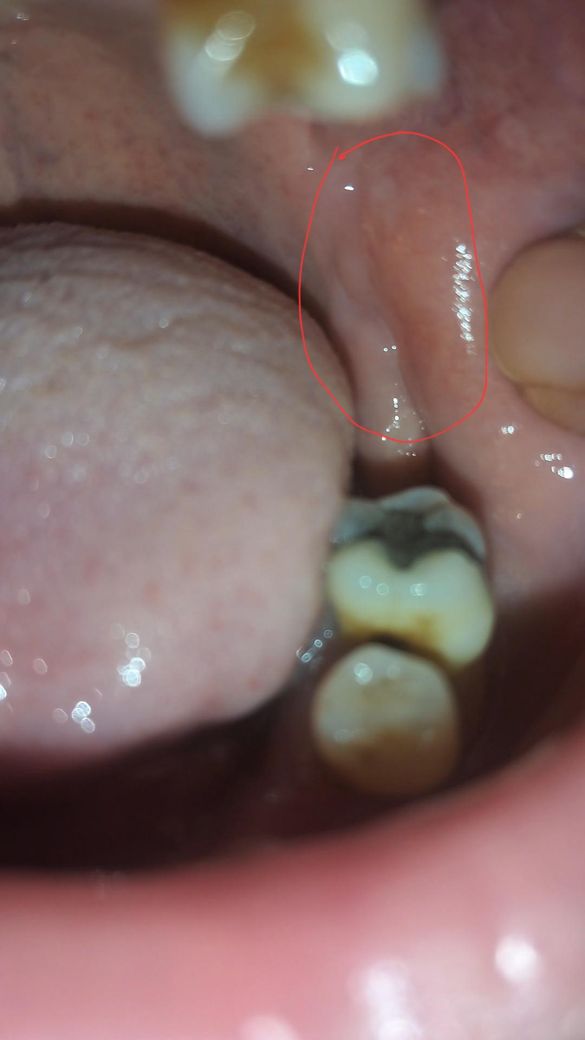

구강백반증인지 봐주세요 전형적인 건 아닌것 같아요

휴대폰 후레쉬로 비추면 안보이는데

동영상 촬영을 누르면 각

도에 따라 살짝 보여요

6개월 정도 됐는데 무심코 넘겼는데 걱정이 되네요

얼마전 혀고 하얗게 되어 있어 백반증 조직검사 받았는데 아나라도 나왔어요